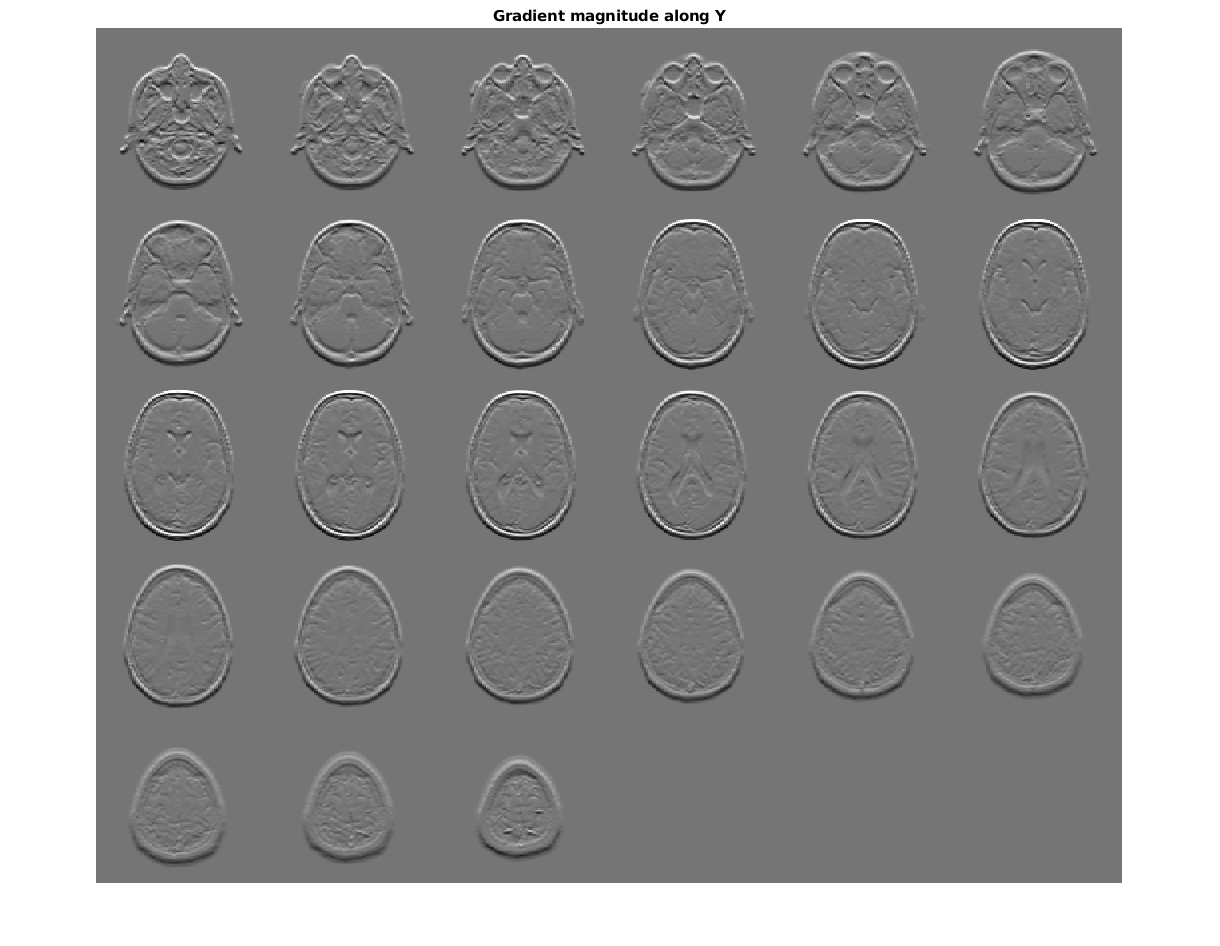

figure, montage(reshape(Gy,sz(1),sz(2),1,sz(3)),'DisplayRange',[])

title('Gradient magnitude along Y')

Figure contains an axes. The axes with title Gradient magnitude along Y contains an object of type image.